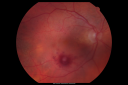

Self Sealed Retinal Arteriol Macroaneurysm 639 viewsFA on presentation showed minimal to no active leakage. Also, there is a small cuff of blood around the MA which is favorable for closure

|